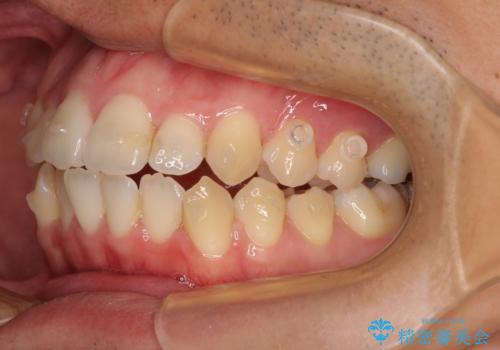

開咬とデコボコを整える インビザライン矯正治療

- 前歯の開咬と叢生を気にして来院された患者様です。

開咬の治療は、前歯を閉じるように動かすとともに、上下臼歯を圧下(骨内にめり込ませる)させることで進めて行きます。

インビザラインは臼歯の圧下を効果的に行えるため、インビザラインを用いて矯正治療を行うこととしました。また、アンカースクリューを用いて、口元の突出感の改善を図りました。